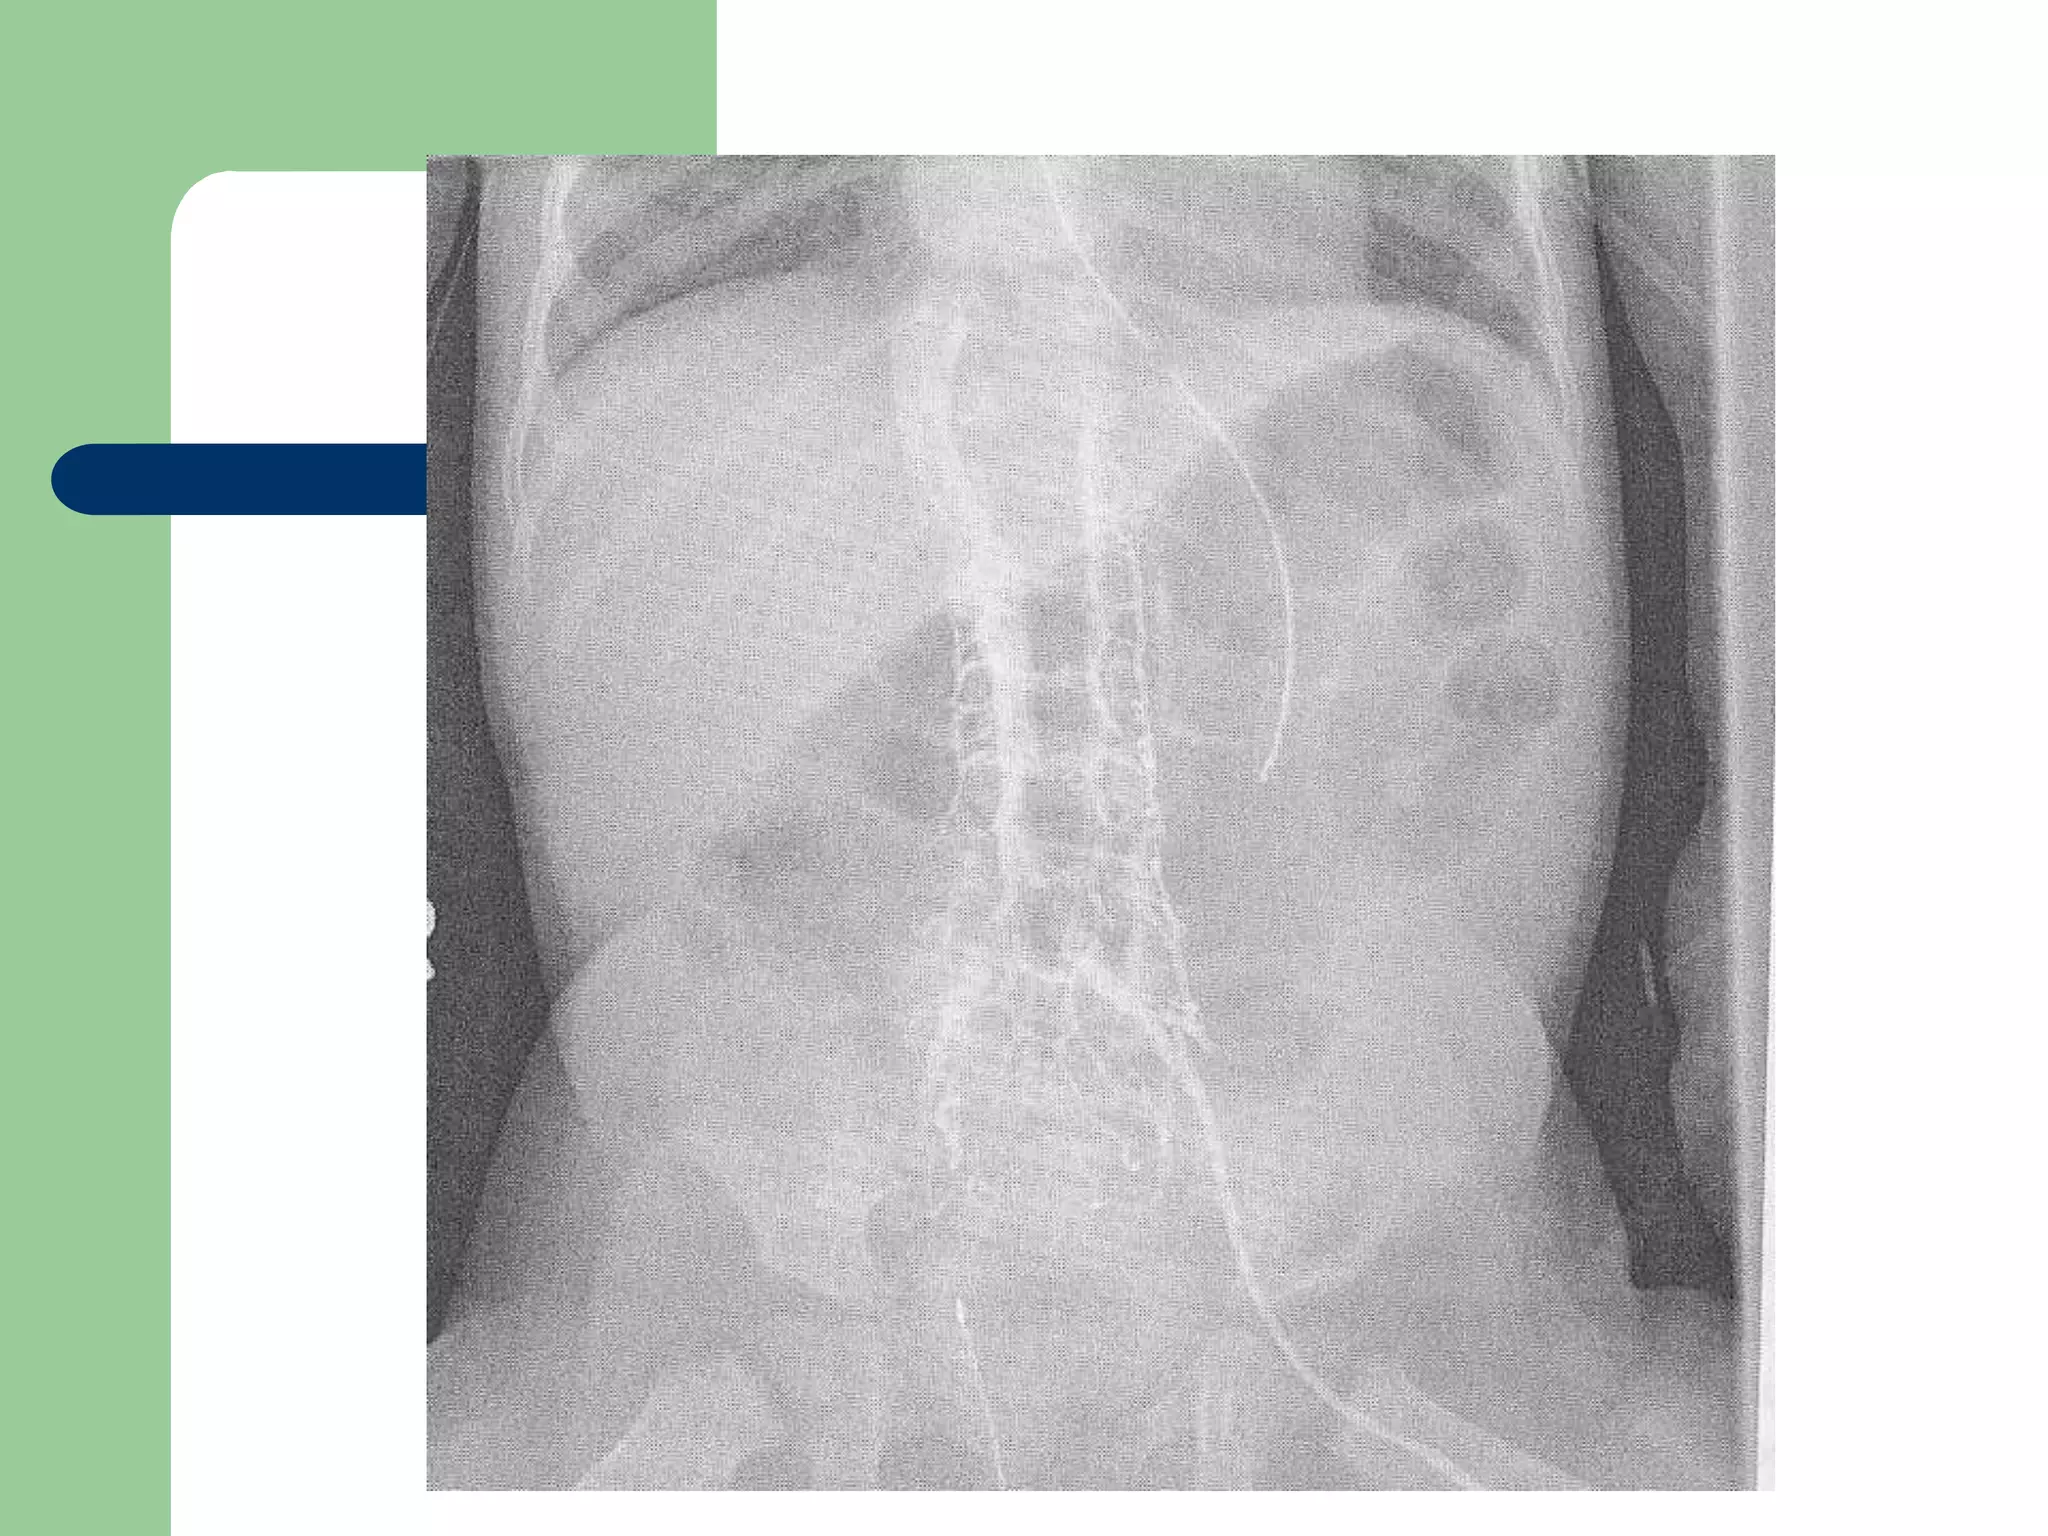

Non-Tunneling – CVC

 Percutaneous catheters

 Also known as: Central Venous Catheters

(CVC)

– Subclavian, femoral or internal jugular

– Single, double or triple lumen

Non-tunneling - CVC

 Tip advanced to superior

vena cava or SVC and

right atrium junction

 As with PICC, appropriate

for patients requiring long

term chemotherapy or

TPN

Non-tunneling CVC subclavian site